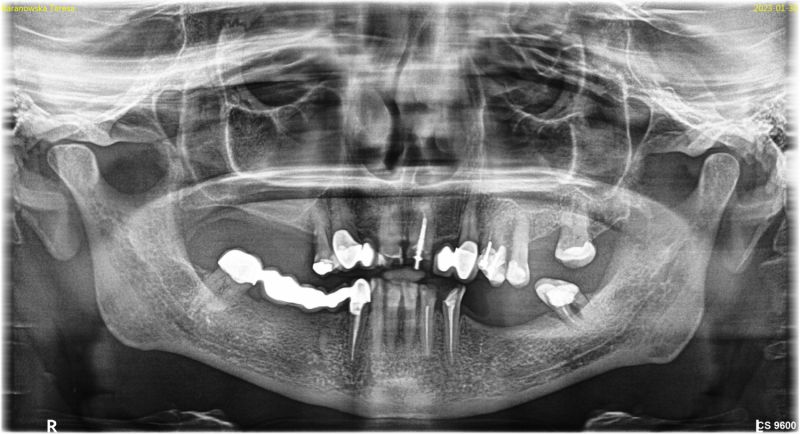

Wykonana praca protetyczna:

- korony pełnoceramiczne na zębach własnych górnych

- korony na implantach w miejscach braków zębów górnych

- mosty na implanatch w łuku dolnym

- odbudowa flow-injection zębów dolnych przednich